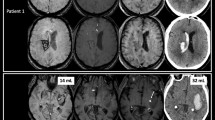

For hematomas associated with neoplasms, the mean VE ratio was 104±15% (mean±standard error; standard deviation 69%; range 7–300%) and the average width of edema 2.4 cm±0.2 cm (standard deviation 0.9 cm) (Figs. 2, 3). The mean VE ratio was 26±2% (standard deviation 12%; range, 5–50%) for hematomas attributed to hypertension or amyloid angiopathy, and 52±10% (standard deviation 42%; range 5–140%) (Figs. 4, 5) for those with vascular malformations. Thus, for non-neoplastic hematomas (spontaneous and vascular malformation groups combined), the mean VE ratio was 37±5% (standard deviation 31%) and average edema width was 0.9±0.1 cm (standard deviation 0.5 cm). Both the VE ratio ( P =0.009) and the width of the zone of vasogenic edema ( P =0.0001) were significantly greater for neoplasm-associated hematomas.

A 7-year-old girl with an acute left temporal lobe hematoma. a Fat-saturated fast spin-echo T2-weighted image shows a hematoma, mean diameter 2.2 cm and a 0.9 cm collar of high signal; the VE ratio is 41%. b Contrast-enhanced T1-weighted image shows a focal area of enhancement ( arrow) corresponding to the nidus of an arteriovenous malformation on angiography

A 78-year-old man with a left superior parietal hematoma. Fast spin-echo T2-weighted image shows a 3.5 cm lobar hematoma ( open arrow). Maximum width of high signal around it ( between small black arrows) is 1.5 cm and the VE ratio is 43%. Contrast-enhanced MRI 3 months later showed no evidence of tumor or vascular malformation